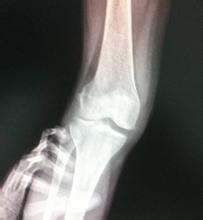

生活上要怎么护理骨性关节炎?骨性关节炎常发生在中老年人身上,多是因为年龄增长因素以及膝关节受损等引起的。骨性关节炎可引起疼痛等,影响较大,因此出现骨性关节炎后要积极护理,护理可以从生活、锻炼等方面入手。下面就让我们一起来看看生活上要怎么护理骨性关节炎。

在疾病发作的急性期要注意休息,同时做好患病部位的保暖工作注意防寒湿,保暖,使膝关节得到很好的休息。尽量减少上下台阶、跑步等使膝关节负重的运动。

另外,在锻炼上也要引起重视。骨性关节炎患者不是不能锻炼,科学有效的锻炼可以减轻骨性关节炎的疼痛,同时,患者要注意不要长时间处于一种姿势,更不要盲目地做反复屈伸膝关节、揉按髌骨、抖晃膝关节等运动,治疗期间请谨遵医嘱。>>>得了骨性关节炎走多久后就要停下来休息了?点击咨询